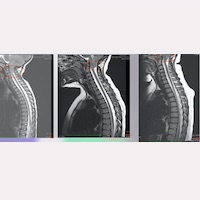

En la casuística del nostre Institut, en algun cas aquest ascens s’observa en 1-2 anys, mentre que en altres casos, al llarg dels primers 5-10 anys postoperatoris (Fig. 1).

El fet que mitjançant una acció quirúrgica indirecta i localitzada en una altra zona anatòmica, es produeixi el canvi de la posició de les amígdales cerebel·loses, juntament amb la millora clínica que experimenten els pacients; pels nostres metges és una confirmació més de què la causa de la patologia s’ha eliminat, deixant de ser activa i de traccionar la mèdul·la, el tronc encefàlic i la columna vertebral.